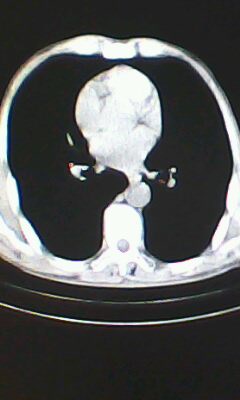

标题: CT26182:男 胸憋 无其它异常症状

胸廓呈桶状,双膈低平,肺实质及纵隔未见明显异常密度灶考虑肺气肿.

肺气肿

做个肺功能检查。肺ct无明显异常。

弥漫性肺气肿 但内胆管轻度扩张